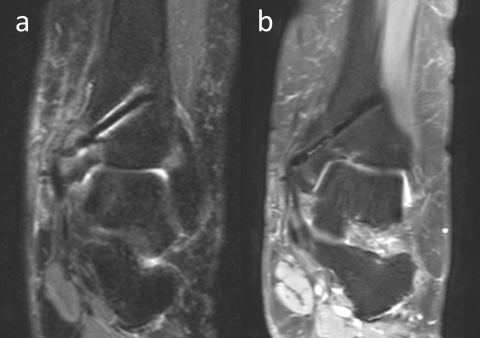

einer osteochondralen Läsion am

Talus einer Innenknöchel-Osteotomie und

Mosaikplastik unterzogen wurde. Die biplanare

Innenknöchel-Osteotomie wurde mit zwei

Magnesiumschrauben fixiert. (a) Die anterior-

posteriore Röntgenaufnahme des Knöchels

am 7. postoperativen Tag zeigt an der Operationsstelle

diffuse Gasansammlungen im

Weichgebe (weiße Pfeile). (b) Koronare und

(c) axiale CT-Aufnahmen mit sichtbarem Gas

(weiße Pfeile).

Läsion am Talus einer Innenknöchel-Osteotomie und Mosaikplastik

unterzogen wurde. PD-gewichtete koronare MRT-Aufnahmen

in den Monaten 3 (a) und 13 (b) zeigen, dass die Artefakte im Laufe der

Zeit abnehmen.